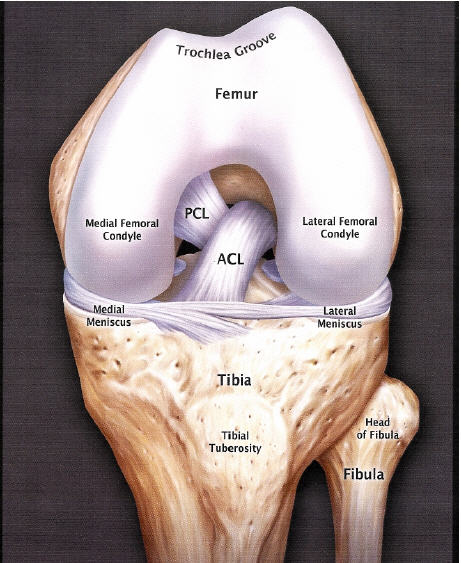

Anatomia ACL

Anatomia ACLW stawie kolanowym stykają się cztery kości: kość udowa, piszczelowa, strzałkowa i rzepka. Rzepka znajduje się bezpośrednio przed stawem kolanowym, zapewniając ochronę i zwiększając siłę mięsnia czworogłowego uda. Więzadła zapewniają połączenia między kośćmi i stabilność stawu. W kolanie występują cztery główne więzadła. Działają jak silne, nieco elastyczne taśmy.

Więzadła poboczne

Znajdują się na zewnętrznych ścianach kolana. Więzadło poboczne przyśrodkowe (MCL - Medial Collateral Ligament) znajduje się po wewnętrznej stronie, natomiast więzadło poboczne boczne (strzałkowe) LCL (Lateral Collateral Ligament) znajduje się po zewnętrznej stronie. Kontrolują one ruchy kolana na boki i przygotowują je na nietypowe ruchy.

Więzadła krzyżowe

Znajdują się wewnątrz stawu kolanowego. Każde z nich krzyżuje się z drugim, tworząc "X" - stąd ich nazwa. Więzadła krzyżowe kontrolują ruchy kolana w przód i tył (nadmierne wysuwanie się piszczeli do przodu i tyłu).

Więzadło krzyżowe przednie biegnie skośnie, ku środkowej części kolana. Zapobiega to wysunięciu się kości piszczelowej przed kość udową, a także zapewnia stabilność obrotową kolana.